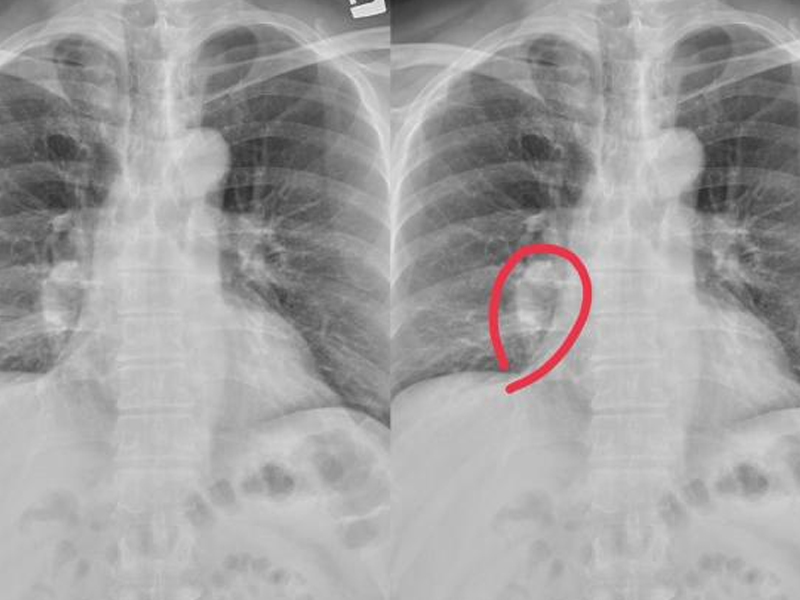

男性一旦到了更年期,可能會有情緒波動大、性功能衰退、遭遇心血管危機、全身肌肉開始鬆弛等症狀出現,之後也會陸續被多種疾病盯上。 男性衰老標誌:「1 臭 2 大 2 小」若沒中,恭喜還很年輕。 1 臭 隨着年齡的增長,男性的體味會逐漸增強,尤其是在夏季或運動後更為明顯。這主要是因為隨着年齡的增長,男性的皮膚和汗腺逐漸失去彈性和活力,從而導致出汗量減少,汗液中的廢物和細菌無法及時排出體外,從而產生臭味。 應對措施:保持良好的個人衛生習慣,如勤洗澡、換衣服、使用除臭劑等。同時,也要注意飲食習慣,避免食用刺激性食物和過多的油膩食物,以減少體味的產生。 2 大 隨着年齡的增長,男性的脂肪堆積和肌肉萎縮會逐漸增加,從而導致體型變大,肚子變大。男性的前列腺功能也會逐漸下降。當出現前列腺肥大、前列腺炎、前列腺增生等情況,並伴隨排尿困難等症狀時,這表明男性已經進入衰老階段,並且衰老程度較重。 此外,男性的骨骼和關節也會逐漸變大,尤其是手指、腳趾等部位。 應對措施:保持良好的飲食習慣,控制體重,避免過度肥胖。同時,也要適當進行運動,增加肌肉量,保持身體的柔韌性和平衡能力。 2 小 對一些男性朋友來說,45 歲以後聽力逐漸下降也是衰老的一個重要標誌。這是因為 45 歲以後,耳道會變窄,耳膜會變厚,從而導致聽力下降。中醫認為:腎通於耳,也與腎的機能衰退有關。 男性 45 歲以後肺活量變小也是衰老的一個重要標誌。隨着年齡的增長,肺部的彈性和容積會逐漸下降,從而導致肺活量逐漸減小。肺活量的大小與人的身體狀況、年齡、性別等因素有關。一般來說,男性的肺活量比女性大,但隨着年齡的增長,男性的肺活量也會逐漸減小。 |